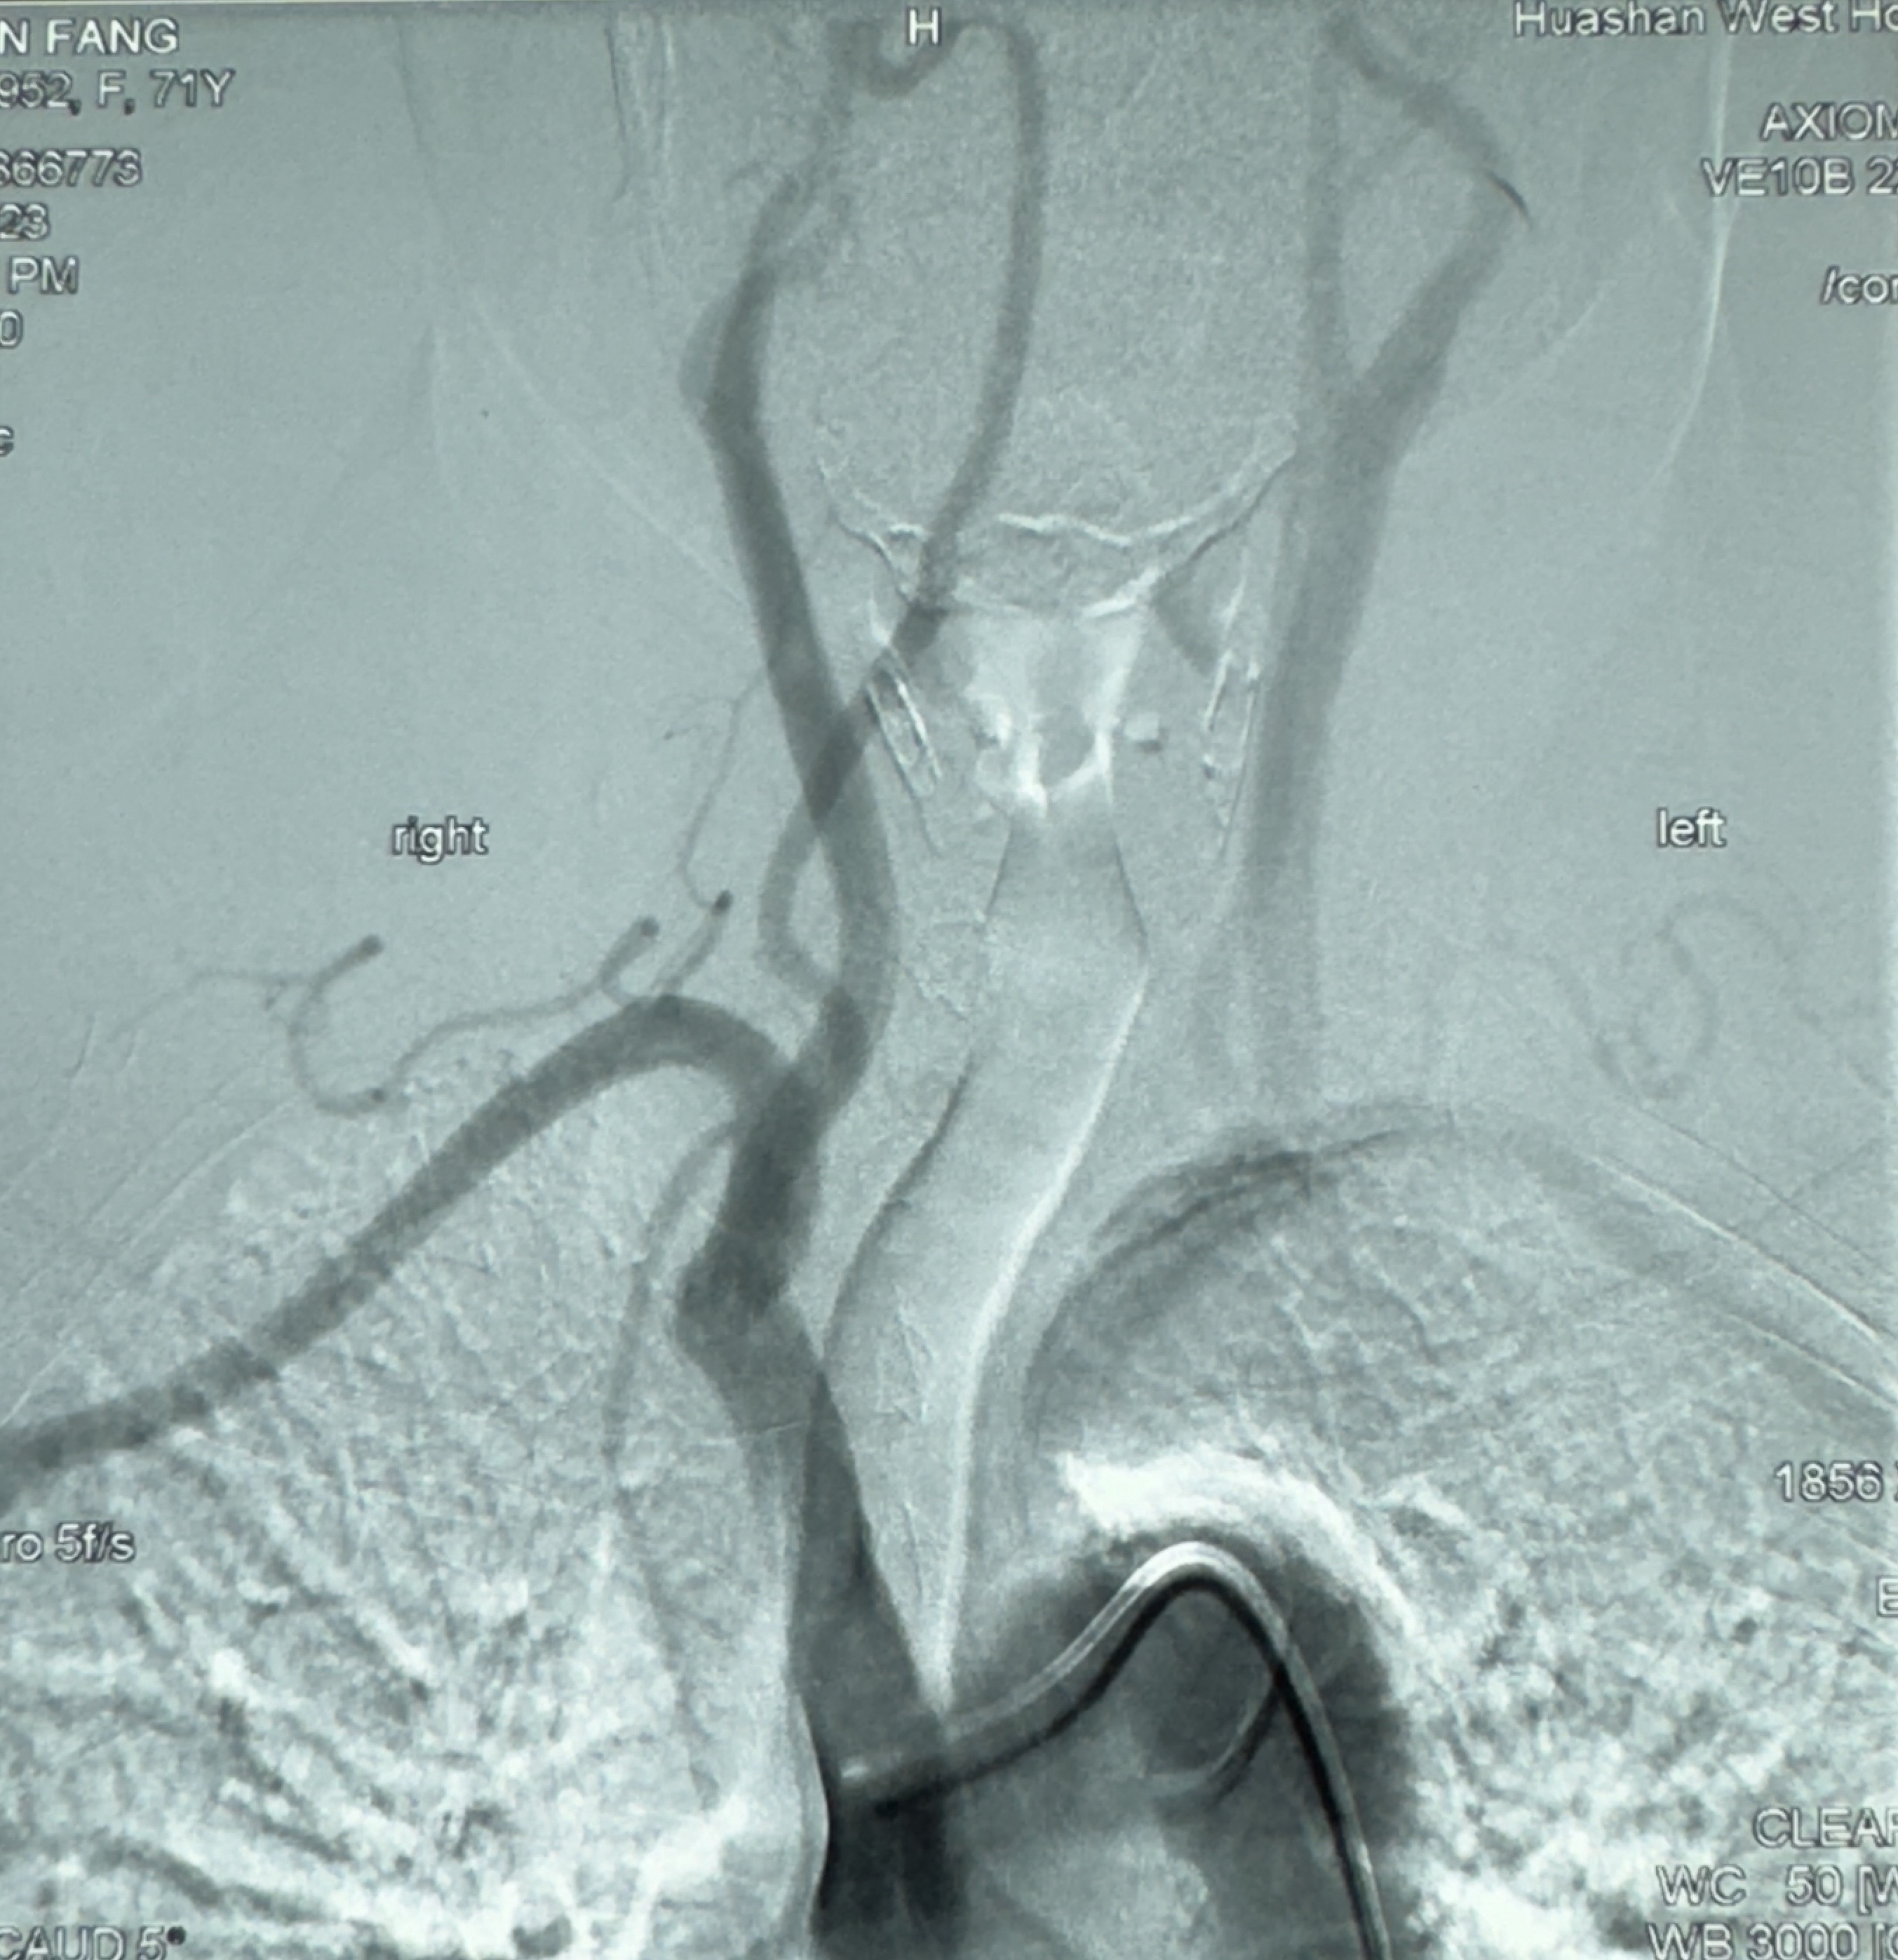

2023-12-08外院DSA:右侧颈眼动脉瘤,约13*12mm大小,压颈试验显示左右向及后向前代偿可